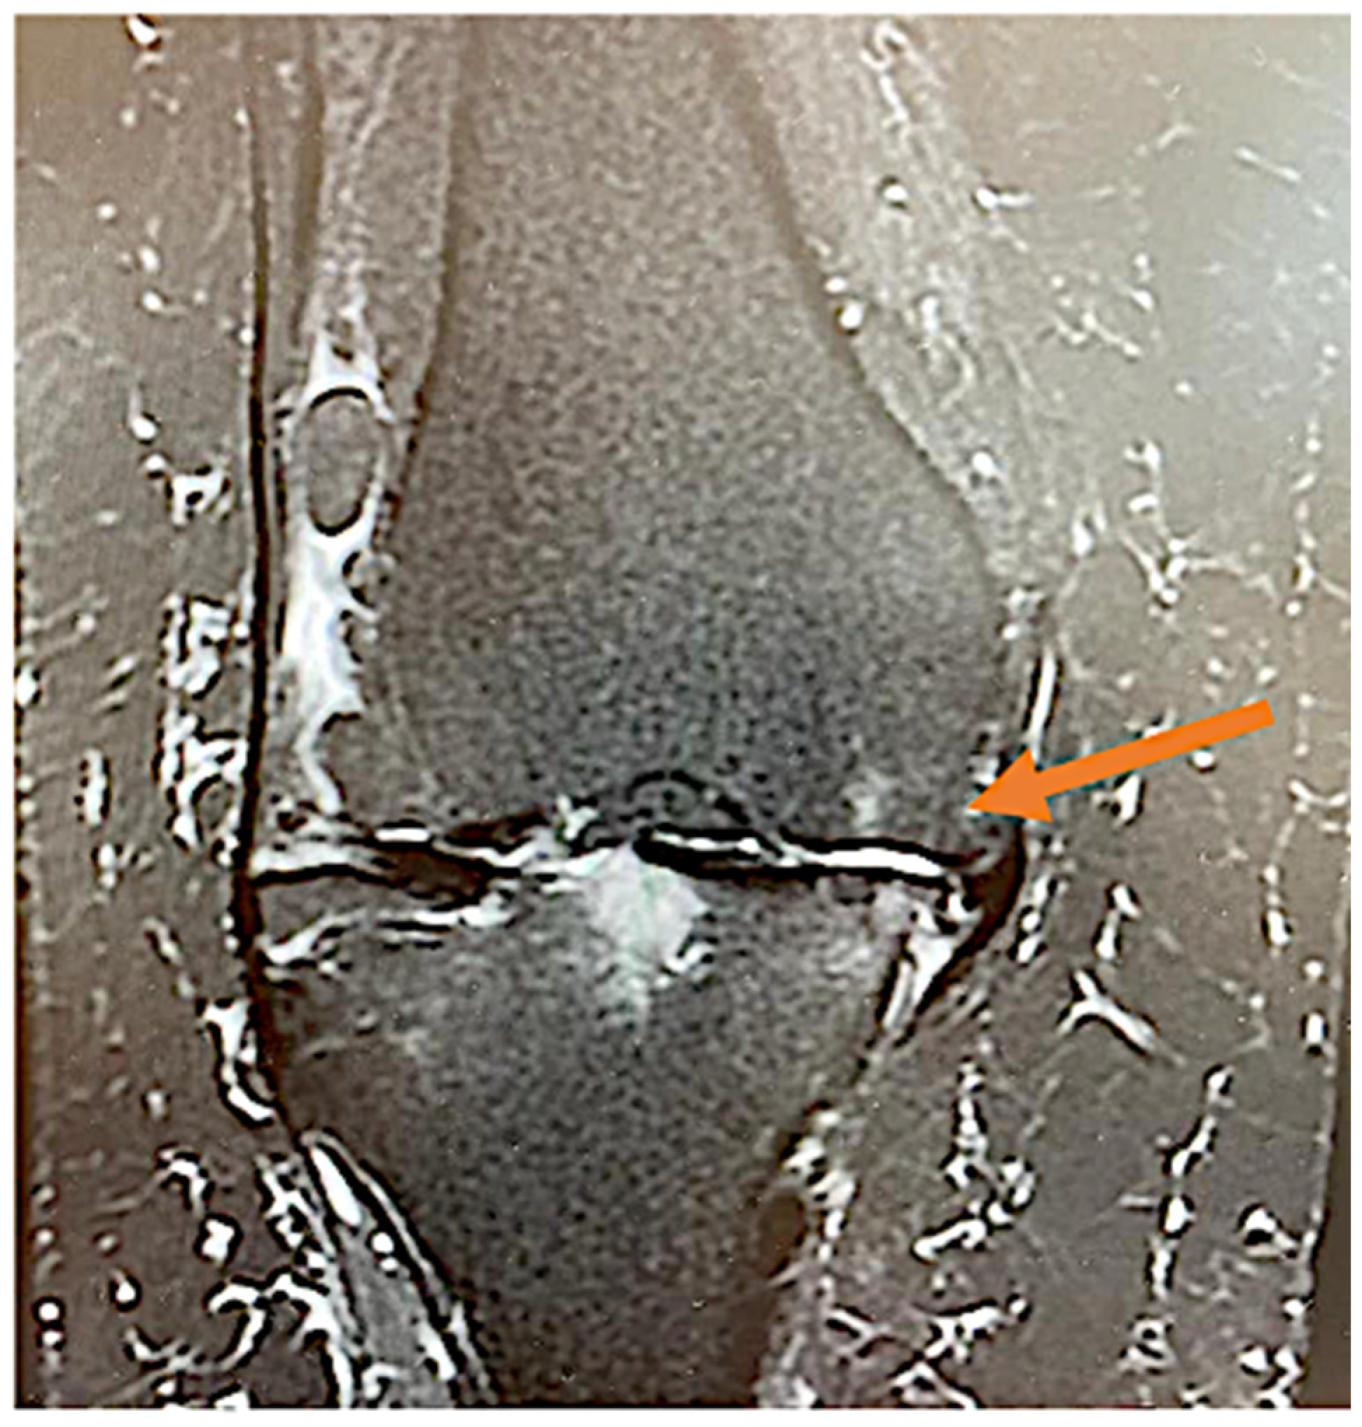

The knee OA Ahlbäck grading was assessed by the senior orthopedic surgeon using plain antero-posterior and lateral view radiographs at the time of physical examination. Magnetic resonance imaging (MRI) evaluation was performed for each patient in order to accurately identify arterial branches responsible for capsular inflammation (as seen in Figure 2).

Figure 2.

Knee coronary MRI STIR sequence highlighting (arrow), a neovascular arterial branch presumably responsible for knee pain in OA.